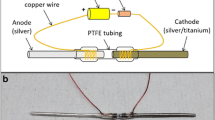

A total of 20 animals were randomly assigned to four experimental groups: VANCO, VANCO + 1STIM, VANCO + 2STIM, or CONT. Each experimental group consisted of five animals. On postoperative Day (POD) 6, the rats in the VANCO, VANCO + 1STIM, and VANCO + 2STIM groups started receiving subcutaneous injections of vancomycin at 150 mg/kg (V8138; Sigma-Aldrich, St Louis, MO, USA) twice a day. This dosing was derived from other experimental models [1, 4, 15, 21, 25] and previous work in our laboratory [19]. On POD 7, all animals were anesthetized and the skin over the lateral cortex of the humerus was incised to expose the end of the Ti rod. Subsequently, an Ag/AgCl pellet reference electrode (E242ML; In Vivo Metric, Healdsburg, CA, USA) and a dual platinum wire counterelectrode (CHI115; CH Instruments, Austin, TX, USA) were placed subcutaneously at an incision site immediately adjacent to the incision site providing access to the Ti rod without disruption or manipulation of the intraarticular IAI (Fig. 2). In the VANCO + 1STIM and VANCO + 2STIM groups, the electrodes were connected to a potentiostat (Ref 600; Gamry Instruments, Warminster, PA, USA) that provided CVCES of −1.8 V (all voltages are versus Ag/AgCl unless otherwise noted) to the Ti rod (working electrode) for 1 hour. Animals in the VANCO and CONT groups had the electrodes placed, but no stimulation was delivered during the sham procedure. After the stimulation/sham procedure, all electrodes were removed, incisions sutured, and the animals were returned to their cages. Animals in the VANCO, VANCO + 1STIM, and VANCO + 2STIM groups continued to receive the 150-mg/kg twice-daily subcutaneous injections of vancomycin. On POD 21 the VANCO + 2STIM group underwent an additional 1-hour CVCES using the same protocol as previously described. After this additional procedure, the rodents continued to receive the 150-mg/kg twice-daily subcutaneous injections of vancomycin.

This schematic shows the in vivo stimulation using a three-electrode system. The Ti implant (working electrode) was accessed through internal cortex incision, whereas Ag/AgCl (reference) and platinum (counter) electrodes were placed subcutaneously adjacent to the Ti implant. (Reprinted from Ehrensberger MT, Tobias ME, Nodzo SR, Hansen LA, Luke-Marshall NR, Cole RF, Wild LM, Campagnari AA. Cathodic voltage-controlled electrical stimulation of titanium implants as treatment for methicillin-resistant Staphylococcus aureus periprosthetic infection. Biomaterials. 2015;41:97–105, with permission from Elsevier.)